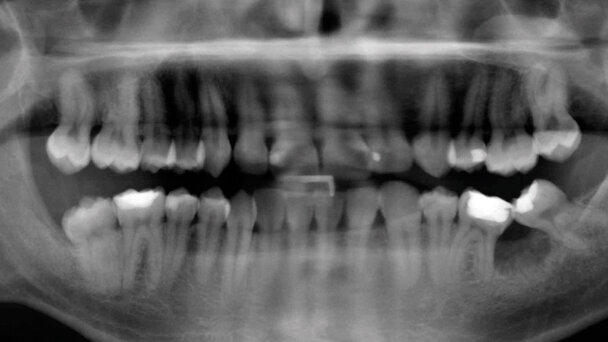

L’aumento della cultura della prevenzione odontoiatrica ha portato un maggior numero di persone a sottoporsi a trattamento ortodontico in età adulta. Tale opzione terapeutica è oggi possibile in seguito all’evoluzione tecnologica dei dispositivi ortodontici e allo sviluppo di nuove modalità di ancoraggio dentale e scheletrico.

Contemporaneamente l’ortodonzia attuale può contare su una maggiore conoscenza dei meccanismi biologici ossei e dei tessuti parodontali, con possibilità di ridurre i rischi a carico della dentatura naturale e ottenere risultati clinici predicibili e stabili nel tempo.

I vantaggi derivanti da un approccio ortodontico in età adulta sono rappresentati dal poter correggere i difetti occlusali riducendo il ricorso alla protesi e, da un punto di vista biologico, l’utilizzo di una forza ortodontica leggera e costante costituisce uno stimolo fisiologico per il trofismo dell’osso alveolare e della gengiva. Infine, l’allineamento dentario consente una più efficace igiene orale domiciliare al paziente, riducendo così l’incidenza dei fattori causali, quali placca e tartaro, nell’insorgenza della parodontopatia. Soprattutto il miglioramento e la conservazione di un’occlusione dentaria naturale e corretta può rappresentare anche la migliore soluzione estetica per il paziente, riducendo al minimo possibili correzioni da effettuare al termine del trattamento ortodontico.